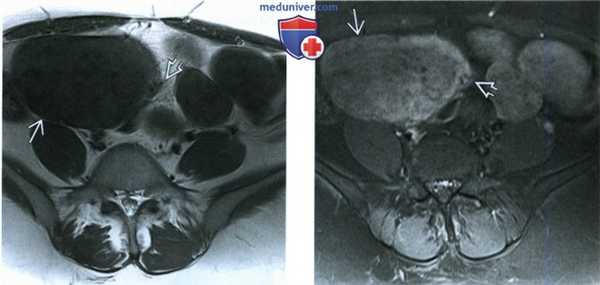

(Слева) При КТ с контрастным усилением в аксиальной плоскости у пациентки 57 лет, которой ранее по поводу миомы матки была выполнена гистерэктомия и которая обратилась по поводу болей в животе и рвоты, выявлены расширенные петли тонкой кишки.

(Справа) При КТ с контрастным усилением в корональной плоскости в проекции максимальной интенсивности у той же пациентки выявлено расширение тонкой кишки и объемное образование в малом тазу. Непосредственно позади объемного образования располагается место перехода расширенной кишки в отрезок ее с нормальным диаметром. Во время операции оказалось, что тонкую кишку сдавливала перекрутившаяся «паразитирующая» миома матки.

(Слева) При КТ с контрастным усилением в аксиальной плоскости у пациентки 22 лет видно крупное мягкотканное образование с нечеткими границами, заполняющее брюшную полость. На операции диагноз диффузного миоматоза матки подтвердился.

(Справа) При МРТ с контрастированием на Т1-ВИ FS в аксиальной плоскости видна увеличенная матка, замещенная миоматозными узлами, накапливающими контрастное вещество и содержащими очаги дегенерации. Во время операции диагноз диффузного миоматоза подтвердился. (Слева) МРТ с контрастированием, Т1-ВИ FS в корональной плоскости у той же пациентки, демонстрирующее степень увеличения миоматозной матки. Границы между узлами, замещающими матку, нечеткие.

(Справа) При МРТ с контрастированием на Т1-ВИ FS в корональной плоскости у пациентки, которая обратилась по поводу объемного образования в животе, выявлена увеличенная матка, замещенная мягкотканной структурой, диффузно накапливающей контрастное вещество. Соответствие образования пролиферирующей гладкомышечной ткани подтвердило диагноз диффузного миоматоза. (Слева) При МРТ с контрастированием на Т1-ВИ FS в аксиальной плоскости у той же пациентки в матке видны участки дегенерации.

(Справа) При МРТ на Т2-ВИ FS в аксиальной плоскости видна увеличенная дольчатая матка, замещенная мягкотканными образованиями, дающими изоинтенсивный сигнал. Исследование операционного материала подтвердило поражение матки доброкачественными миоматозными узлами.